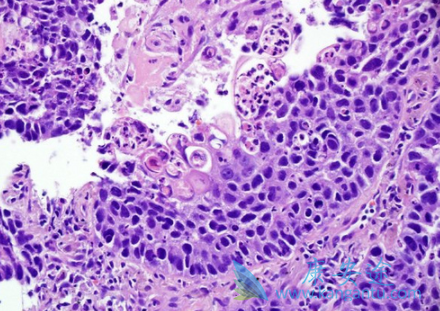

肺鳞状细胞癌约占非小细胞肺癌(NSCLC)的30%,90%与吸烟有关,中央型多见,倍增时间较长。虽然肺鳞状细胞癌及肺腺癌均发生于同一器官,但在基因组学方面有显著差别。目前,肺鳞状细胞癌仍缺少可利用的基因突变,肺鳞状细胞癌的靶向治疗研究进展缓慢。那目前肺鳞状细胞癌的治疗药物有哪些呢?